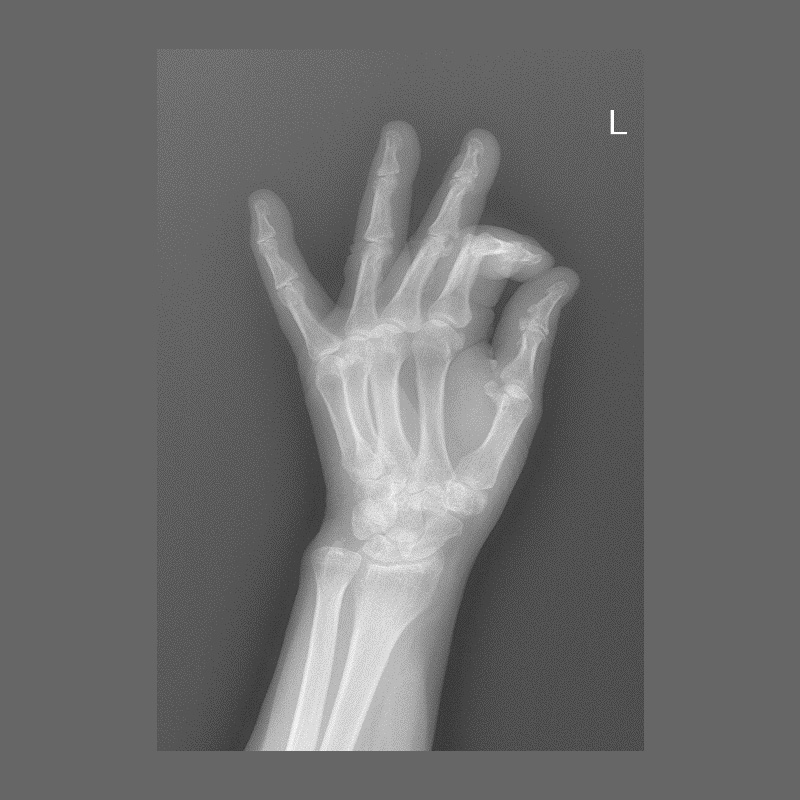

КЛІНІЧНА ГАЛЕРЕЯ GENÈVE 40M: